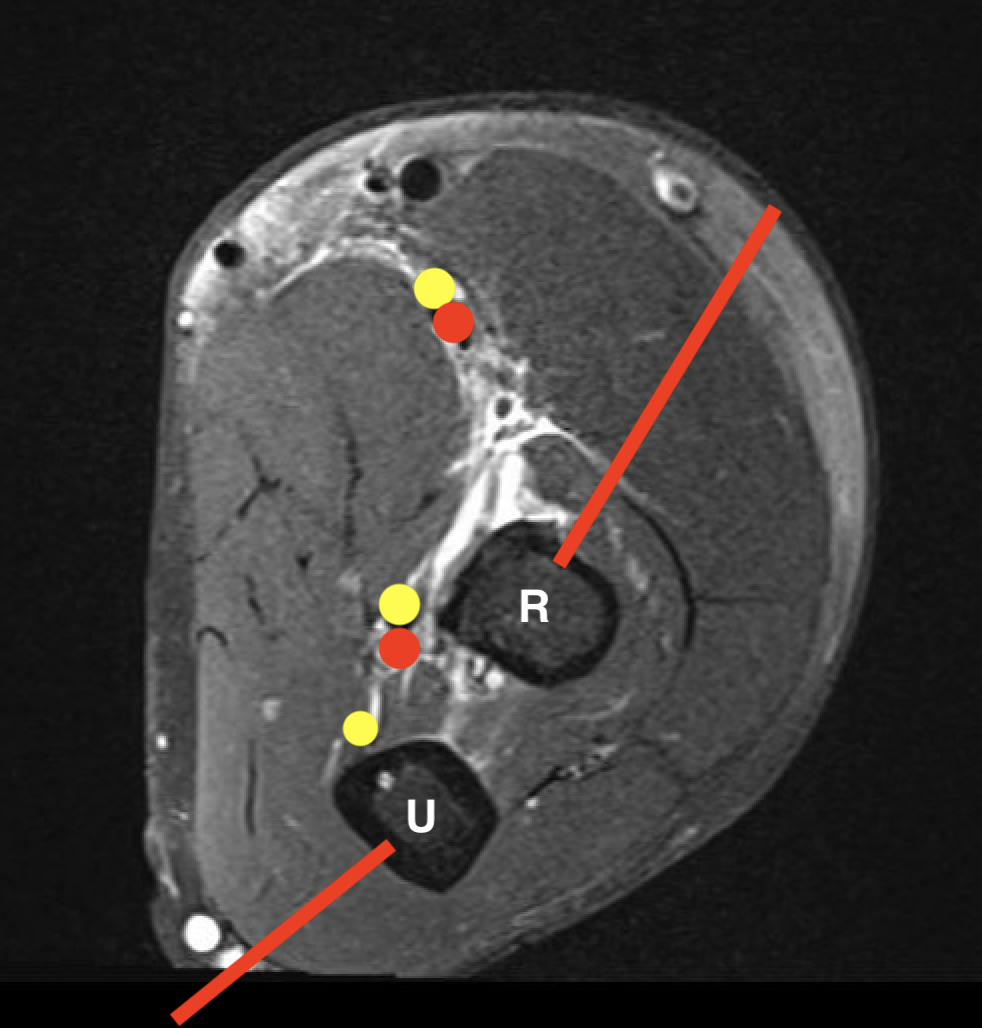

Radius and Ulna

Radius Ulna

Proximal - posterolateral Olecranon - direct posterior

Shaft - direct lateral Ulna shaft - direct medial

Distal radius - direct lateral

Ulna tumourUlna biopsy

GCT distal radiusDistal radius biopsy